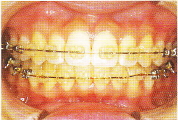

○ホワイトワイヤー(透明な装置に白いワイヤー)

目立たない透明な装置に加え、白いワイヤーを利用することで、より人目を気にせずに矯正治療を行う事が可能になりました。